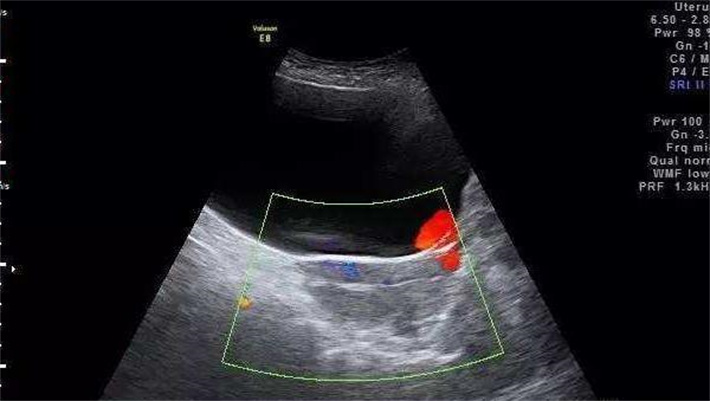

3.阴超检查可以直观呈现女性子宫、卵巢的形态、大小以及卵泡的发育情况,查看是否存在子宫畸形、卵巢囊肿、子宫异常病变等影响生育的疾病。